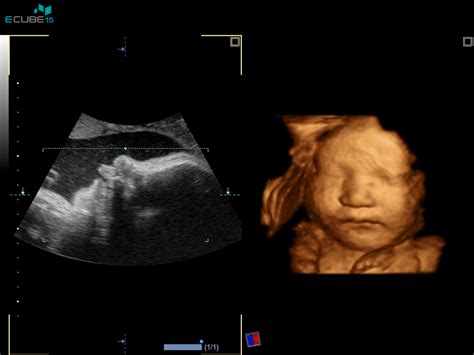

- Oči in okostje: Očesni premiki postajajo vidni na ultrazvoku, okostje pa se utrjuje iz hrustanca v kost.